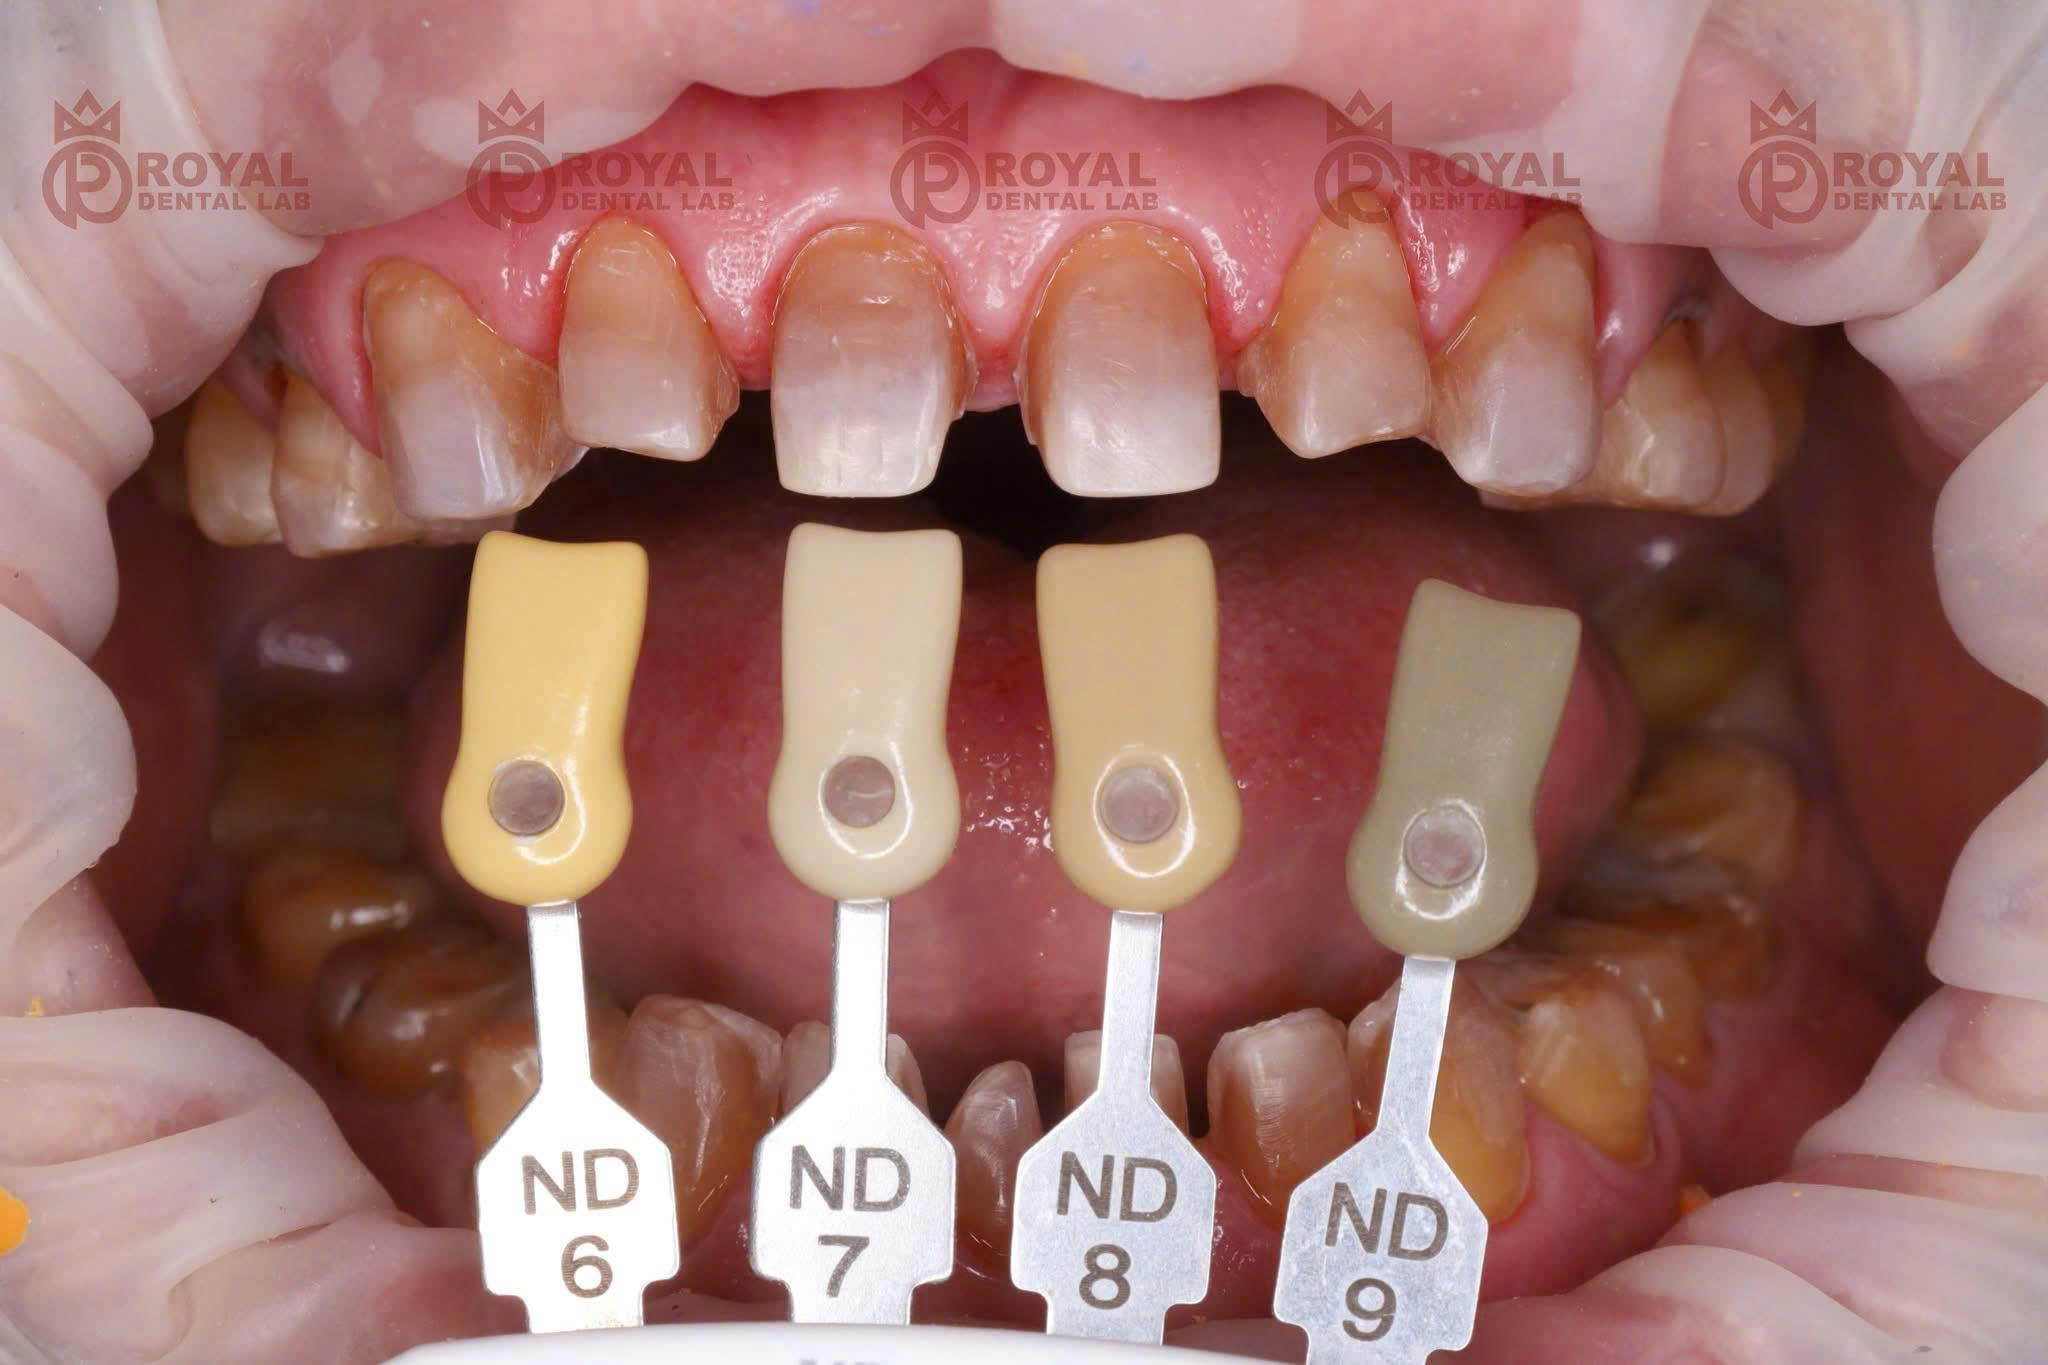

Trong ca lâm sàng do Royal Dental Lab thực hiện, bệnh nhân gặp tình trạng khớp cắn ngược. Do đặc thù sai khớp cắn, lực nhai của bệnh nhân rất mạnh, có thể lên đến $1000N$. Điều này đòi hỏi vật liệu phục hình phải cực kỳ bền bỉ.

Khả năng che màu hoàn hảo: Với những cùi răng bị nhiễm màu hoặc sẫm màu, Zirconia tiền nung kết giúp che phủ hoàn toàn. Phục hình sẽ có màu sắc đồng nhất, không bị ánh xám.